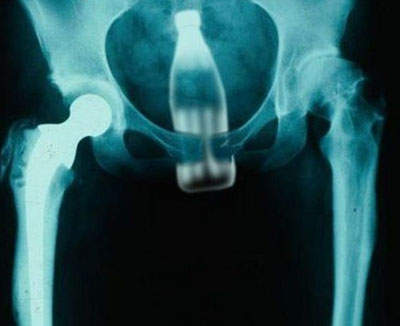

大家想想看x光照片中.....

(有一瓶可口可樂在你的身體裡.....是有多恐怖!)